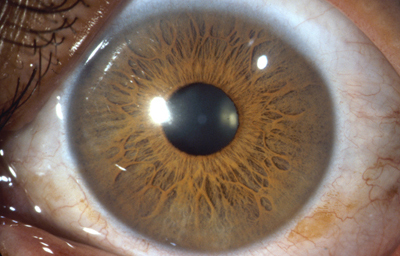

Separa la cámara Anterior de la cámara Posterior en el Ojo, y esta situado por delante del Cristalino; se compone de 3 capas: la hoja Anterior del Iris (membrana pupilar) cuya atrofia parcial genera las criptas de Fuch´s, el Estroma, capa fibrovascular y pigmentada, no tiene epitelio y su origen es mesodérmico; la Posterior debajo del estroma, es una capa de células epiteliales pigmentadas con un grosor de 2 células, conocida como el Epitelio pigmentario del Iris cuyo origen viene del neuroectodermo.

1- La Zona Pupilar es la región mas interna que conforma el borde de la pupila ;(desde el borde periférico del collarete)

2- La Zona Ciliar es el resto del iris y se extiende hasta su origen en el cuerpo ciliar

El Collarete que separa la zona pupilar de la ciliar y es la porción mas gruesa del iris, es un vestigio de la cubierta de la pupila embrionaria. La Raiz de iris es la porción mas periférica y la mas delgada, esta unida a la esclera y a la porción anterior del Cuerpo Ciliar. El Iris y el Cuerpo Ciliar componen la Úvea Anterior.

En la cara Anterior esta el pigmento que le da el color al Iris y dependiendo del grado de reabsorción u atrofia de esa capa anterior se pueden observar:

Las Criptas de Fuchs: que son pequeñas aberturas alrededor del collarete, producto de la atrofia o reabsorción de la hoja anterior del iris, que le permiten al estroma y a los tejidos mas profundos estar en contacto con el humor acuoso.

Cuando el Iris no tiene criptas, se considera que la reabsorción u atrofia de la hoja anterior (memb. pupilar) se detuvo en el circulo menor.